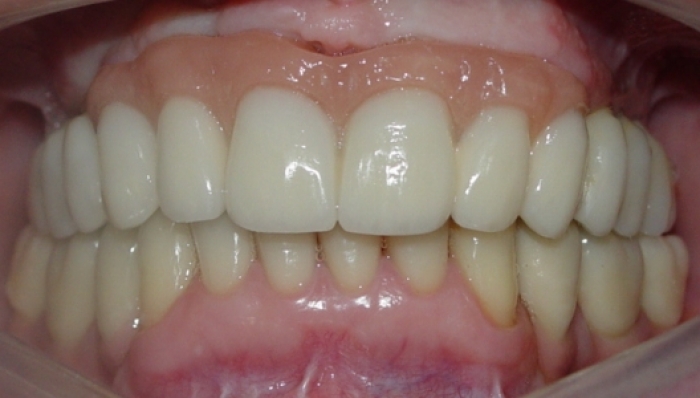

Prótese fixa instalada sobre implantes

Sorriso do caso finalizado em novembro de 2010